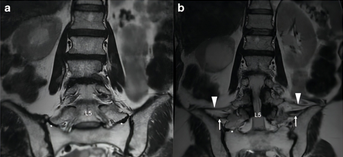

椎弓根钉误置引起的迟发性术后神经损害

椎弓根钉准确性的CT评价方法主要有如下几种。置钉失败可造成灾难性的后果,估计大家都听过坊间传闻:那个医院钉子打穿了主动脉,那个大腕钉子打瘫了脊髓。打瘫了基本上麻醉醒了就知道了,很少发生钉子碰到脊髓慢慢发生神经症状的情况。